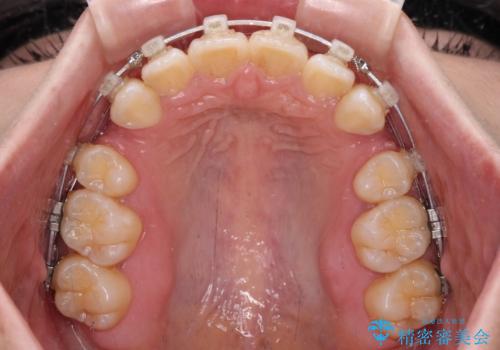

- クリアブラケット

- 前歯の出っ歯と口元の閉じにくさを気にして来院された患者様です。

口元を積極的に引っ込めるために、上下左右の小臼歯4本を抜歯し、目立たないワイヤー装置にて矯正治療を行うこととしました。

上下前歯の歯軸の角度が大きく改善され、お口を閉じたときに顎先に認められた梅干し様の皺も改善されました。